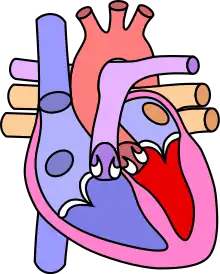

![]() | |

| Diagram of a healthy heart and one with tetralogy of Fallot | |

Tetralogy of Fallot (TOF), formerly known as Steno-Fallot tetralogy,[9] is a congenital heart defect characterized by four specific cardiac defects.[4] Classically, the four defects are:[4]

- pulmonary stenosis, which is narrowing of the exit from the right ventricle;

- a ventricular septal defect, which is a hole allowing blood to flow between the two ventricles;

- right ventricular hypertrophy, which is thickening of the right ventricular muscle; and

- an overriding aorta, which is where the aorta expands to allow blood from both ventricles to enter.

Four malformations

"Tetralogy" denotes four parts, here implying the syndrome's four anatomic defects.[2] This is not to be confused with the similarly named teratology, a field of medicine concerned with abnormal development and congenital malformations (including tetralogy of Fallot). Below are the four heart malformations that present together in tetralogy of Fallot:

| Pulmonary Infundibular Stenosis | A narrowing of the right ventricular outflow tract. It can occur at the pulmonary valve (valvular stenosis) or just below the pulmonary valve (infundibular stenosis).[4] Infundibular pulmonic stenosis is mostly caused by the overgrowth of the heart muscle wall (hypertrophy of the septoparietal trabeculae),[41] however, the events leading to the formation of the overriding aorta are also believed to be a cause. The pulmonic stenosis is the major cause of the malformations, with the other associated malformations acting as compensatory mechanisms to the pulmonic stenosis.[42] The degree of stenosis varies between individuals with TOF and is the primary determinant of symptoms and severity. This malformation is infrequently described as sub-pulmonary stenosis or subpulmonary obstruction.[43] |

| Overriding aorta | An aortic valve with biventricular connection, that is, it is situated above the ventricular septal defect and connected to both the right and the left ventricle. The degree to which the aorta is attached to the right ventricle is referred to as its degree of "override." The aortic root can be displaced toward the front (anteriorly) or directly above the septal defect, but it is always abnormally located to the right of the root of the pulmonary artery. The degree of override is extremely variable, with 5-95% of the valve being connected to the right ventricle.[41] |

| Ventricular septal defect (VSD) | A hole between the two bottom chambers (ventricles) of the heart. The defect is centered around the most superior aspect of the ventricular septum (the outlet septum), and in the majority of cases is single and large. In some cases, thickening of the septum (septal hypertrophy) can narrow the margins of the defect.[41] |

| Right ventricular hypertrophy | The right ventricle is more muscular than normal, causing a characteristic boot-shaped (coeur-en-sabot) appearance as seen by chest X-ray. Due to the misarrangement of the external ventricular septum, the right ventricular wall increases in size to deal with the increased obstruction to the right outflow tract. This feature is now generally agreed to be a secondary anomaly, as the level of hypertrophy tends to increase with age.[44] |